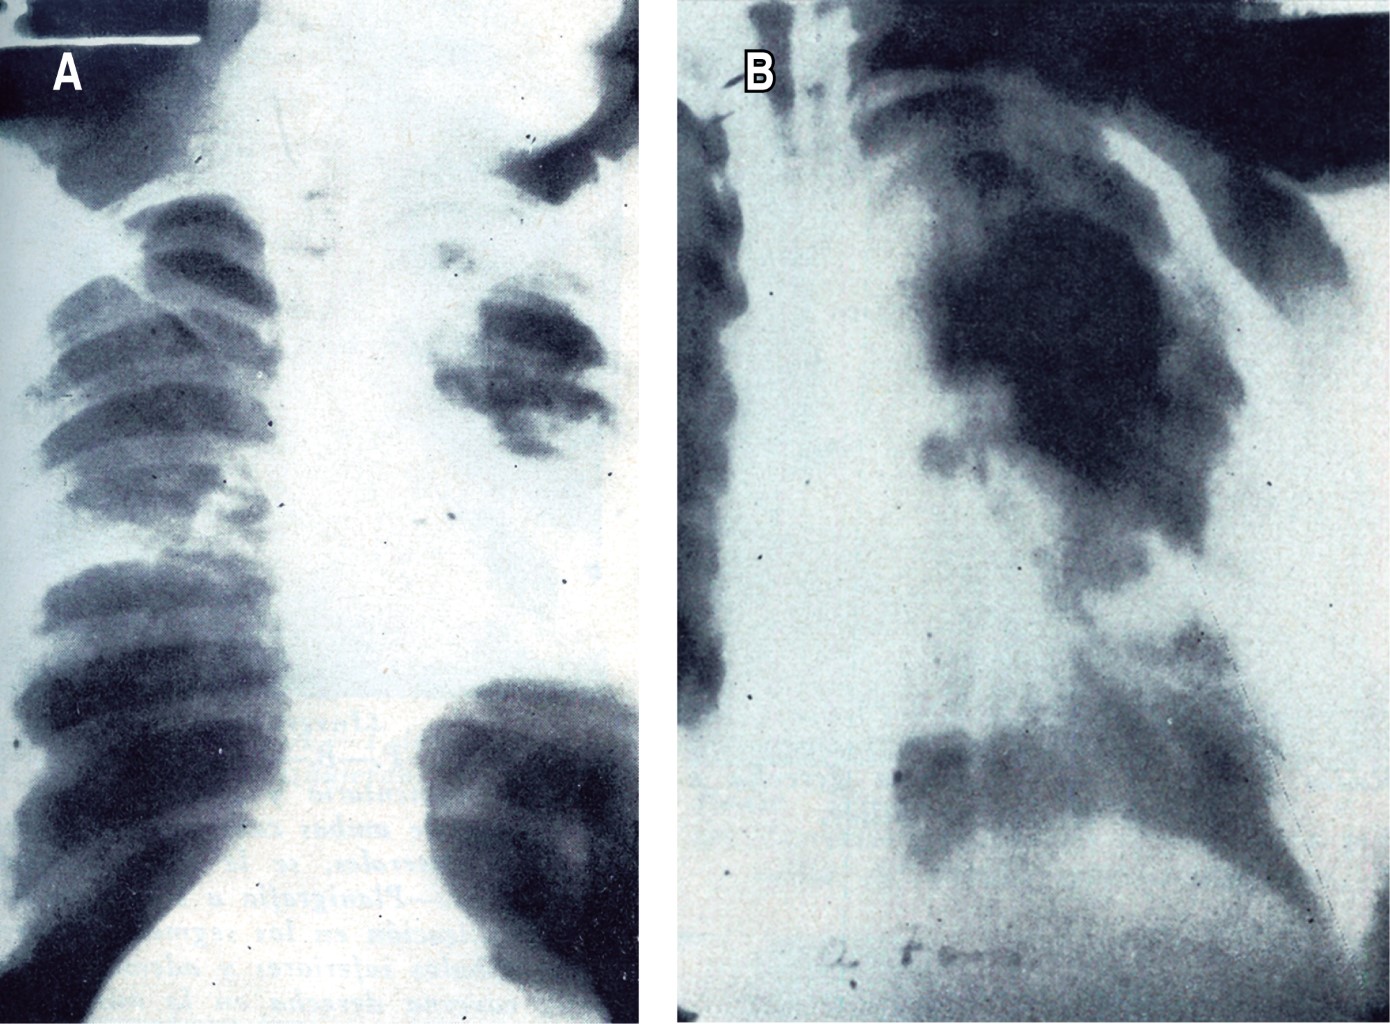

El médico de origen brasileño Manuel Díaz de Abreu4 revolucionó el seguimiento de los pacientes con tuberculosis, como lo narra en su artículo titulado "El registro fluorográfico, base de la profilaxia de la tuberculosis", publicado en NCT en 1945; describe al examen fluoroscópico como técnica y económicamente disponible para enfrentar el amplio problema del sistema de salud en masas, así como el impacto en la epidemiología tuberculosa que podría tener la comprobación fluoroscópica de la enfermedad residual en el paciente con persistencia sintomática. Finalmente, en 1952, Aradio Lozano Rocha5 del Sanatorio de Huipulco (INER) publica en NCT su artículo "Utilidad clínica de la planigrafía en la tuberculosis pulmonar". La planigrafía es lo que hoy conocemos como tomografía lineal, la cual mostraba mayor utilidad en la evaluación prequirúrgica de los pacientes con tuberculosis (Figura 3); explica las posiciones, la extensión, la distancia, la distribución y la semiología de las cavernas.